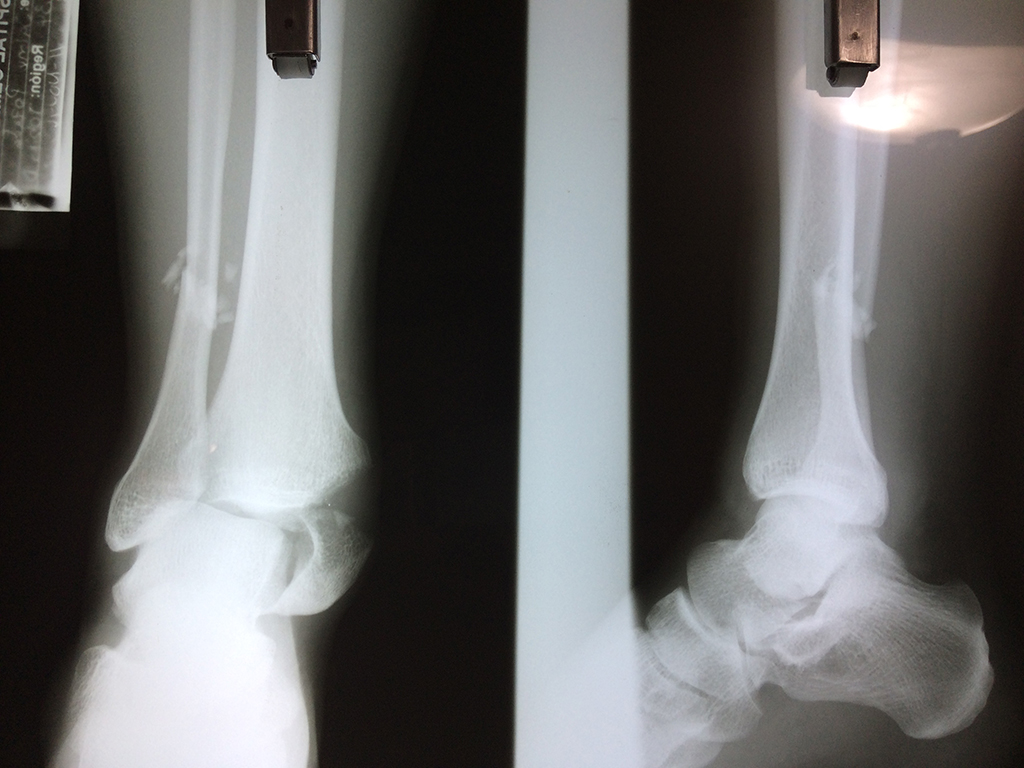

Una fractura de tobillo es la rotura de uno o más de los huesos del tobillo. Estas fracturas pueden ser:

- Parciales (el hueso está sólo parcialmente fisurado, no del todo).

- Completas (el hueso está perforado y está en 2 partes).

- Producirse en uno o ambos lados del tobillo.